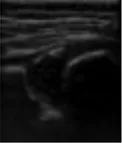

In this study, the weights of each anatomical structure obtained by entropy weight method were respectively bony rim point: 0.29, lower iliac limb point: 0.41, glenoid labrum: 0.30. That means the last weighted score of ultrasound image quality = bony rim point × 0.29 + lower iliac limb point × 0.41 + glenoid labrum × 0.30 (Figure 4). And the proportion of the final weighted score of ultrasound image lower than 3 in each month were 16%, 20%, 14%, 14%, 33%, 27%, 43%.

FIGURE 4

www.frontiersin.org

Figure 4. (A) The image structure of the 5-month-old subject was not clearly displayed, scoring only 2.30. (B) In contrast, the 8-month-old subjects had a clearly displayed image structure, achieving a score of 4.01.